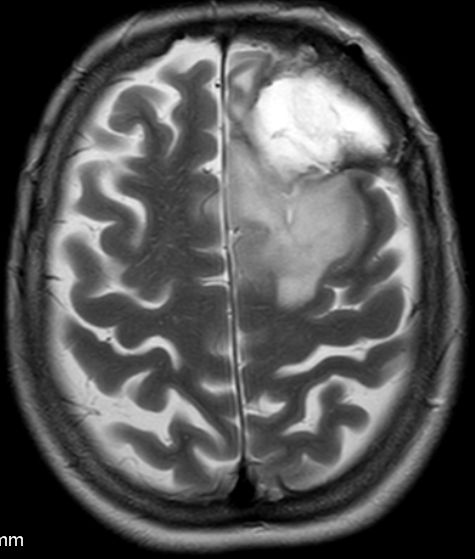

61-jährige Frau mit einem diffusen Astrozytom Grad II | ||

Primärbefund |

MRT T2 Tse |

MRT T2 Tse![]() |